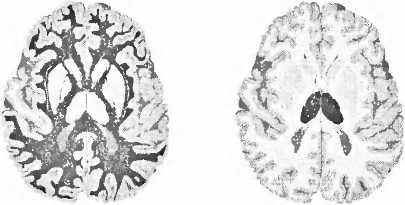

Мы осознаём наше окружение и себя самих. Некоторые структуры мозга имеют решающее значение для этого осознания: кора больших полушарий, таламус, куда стекается информация от наших органов чувств, и белое вещество — нервные волокна между структурами (рис. 19). После инсульта в правом полушарии может быть частично затронуто как самосознание, так и осознание окружающего пространства. В некоторых случаях больной не осознает свое левостороннее поражение и игнорирует как в окружающем пространстве, так и в своем собственном теле всё, что находится слева. Это состояние обозначают как неглект (игнорирование). Если вы подойдете слева к кровати больного, он вас не воспринимает, хотя может поворачивать голову и может вас видеть. Читая газету, больной видит только правую сторону. Рисуя часы, кошку или цветок, он изображает только их правую часть. С тарелки он съедает только то, что лежит в ее правой половине; если же повернуть тарелку на 180°, он съедает и вторую половину порции. Игнорирование может затронуть и левую часть собственного тела. Тогда свою левую руку или левую ногу он не воспринимает как свои собственные. Больной не одевает и не моет свою левую сторону и причесывает волосы только справа.

Рис. 19. Для сознания важны три здоровые и хорошо функционирующие структуры мозга, здесь они помечены черным. Слева — здоровая кора больших полушарий. Справа — таламус. Посредине — белое вещество, где осуществляется связь между корой и таламусом.